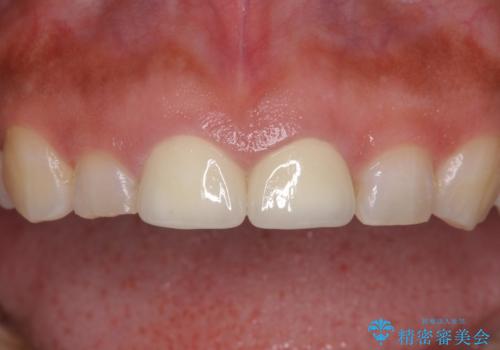

虫歯で神経を取り除いたことによる変色や充填物の着色などが認められたため、オールセラミッククラウンにて補綴することとしました。

また、咬耗により周囲の歯がすり減ったことで、前歯2本のみが長く見えていたため、周囲に長さを合わせることとしました。

治療を提供する側からすると、歯が短すぎるように思えますが、患者様としては長年気になっていた形態が改善され、大変満足していただきました。